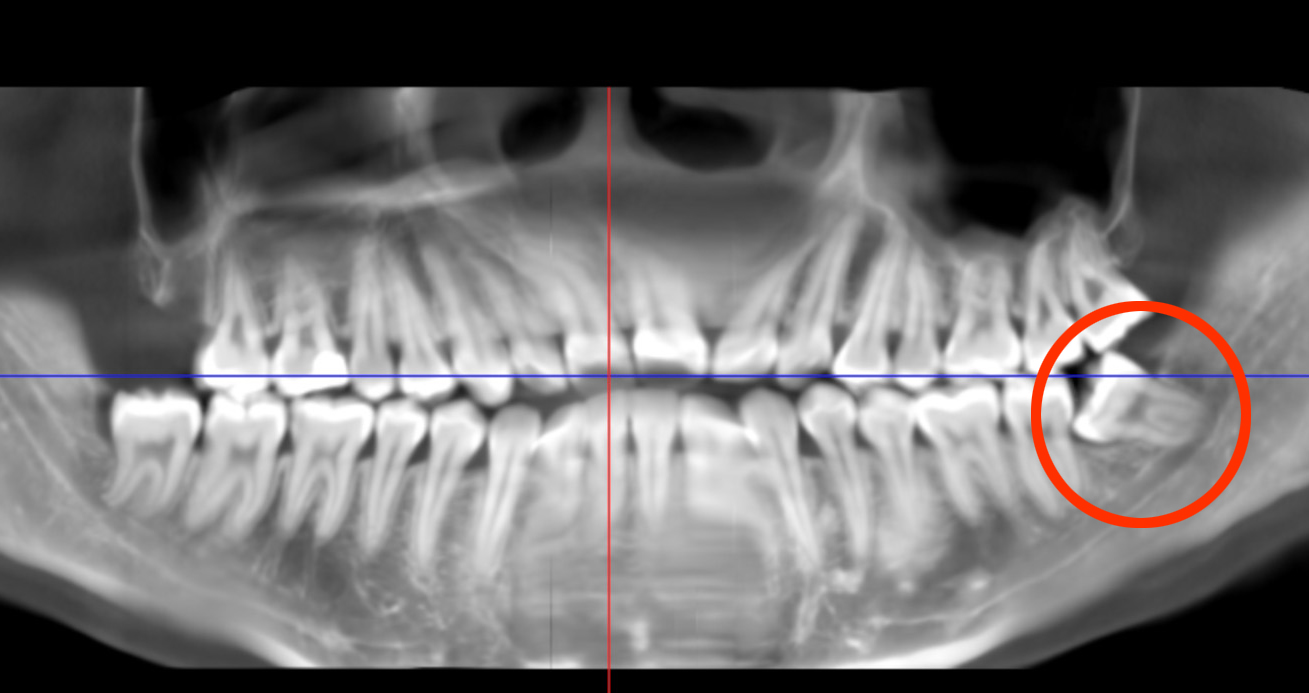

检查显示,崔小姐左侧下颌智齿阻生,紧贴下牙槽神经管